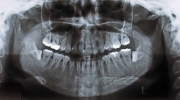

日本矯正歯科学会専門医課題症例(第4症例)

カテゴリー:ClassⅡ division 2 malocclusion (Overbite 5mm以上; 抜歯症例)

出題基準:大臼歯関係がclass Ⅱで、上顎中切歯1本を含む2本以上が舌側傾斜(U1-SN 90度以下)、犬歯関係もclass Ⅱであること。ただし、日本人では症例が少ないことを考慮して、U1-SN 100度以下のclass Ⅱ過蓋咬合も認める。抜歯・非抜歯は問わない。

出題の意味:このケースの条件は一般の人には理解しにくいところがある。通常出っ歯というと上の前歯が外に向かっていることを想像するのが普通であるが、U1-SNが90度以下というのは、上の前歯は内側に傾いていることを示している。なんで??。つまりこれは骨格性上顎前突と考えられるもので、上顎が歯並びごと全体が前へ出ていて、それだと上下の前歯があまりにも離れてしまうため、上の前歯が内側に倒れて下の前歯と何とか接触しようとしている状態と考えられる。

しかし、出題基準にも書いてあるように、このケースは欧米の白人によく見られるケースで、東洋人にはきわめて稀である。そこで類似ケースとして過蓋咬合(かがいこうごう)のケースを代替えとして認めるという配慮をしている。過蓋咬合とは非常に強く深く咬んでいる状態を言う。Overbiteとは前歯の垂直的な重なり具合を示す数値で、5mm以上だと上の前歯が下の前歯をほとんど覆い尽くしている感じになるので、前から見ると下の前歯はほとんど見えない状態になる。こういう状態が典型的な過蓋咬合である。典型的なclassⅡ,division 2のケースは過蓋咬合を合併している。